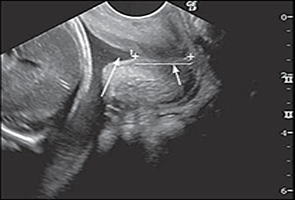

img2 Siêu âm ngã âm đạo (Transvaginal ultrasound-TVU) là một phương tiện hữu ích giúp chúng ta đánh giá sự thay đổi của cổ tử cung (CTC) trong suốt thai kỳ. Qua các nghiên cứu, người ta nhận thấy khi chiều dài kênh CTC ngắn trong tam cá nguyệt (TCN) 2 thì nguy cơ sinh non tự phát tăng. Trước 14 tuần tuổi thai, chiều dài kênh CTC ít có giá trị lâm sàng. Tuy nhiên trong một vài trường hợp đặc biệt như có tiền căn sinh non, tiền căn thủ thuật trên CTC (sinh thiết, khoét chóp ...), CTC ngắn ở thời điểm 10-13 tuần sẽ kết hợp với nguy cơ sanh non tự phát cao. Thời điểm thích hợp để đo chiều dài kênh CTC dựa trên tiền căn sản khoa của thai phụ. Đối với những thai phụ có tiền căn sinh non nên được thực hiện lúc 14-16 tuần, ngược lại nếu không có tiền căn sinh non thì thời điểm phù hợp là 18-23 tuần 6 ngày. Chiều dài kênh CTC thường ổn định ở thời điểm 14-28 tuần và ngắn dần sau 28-32 tuần. Thời điểm thai từ 14-28 tuần, CTC có dạng hình chuông và chiều dài ở :

Chiều dài kênh CTC trung bình thời điểm thai 22 tuần là 40 mm, từ 22-32 tuần là 35 mm và giảm xuống còn 30 mm sau 32 tuần. Các yếu tố như số lần sanh, chủng tộc, chiều cao của thai phụ ít có ảnh hưởng đến chiều dài kênh CTC. Định nghĩa CTC ngắn đã có nhiều thay đổi theo thời gian. Trong nhiều nghiên cứu, người ta nhận thấy chiều dài kênh CTC nhỏ hơn bách phân vị thứ 10 (< 25 mm) kết hợp với việc tăng nguy cơ sanh non tự phát. Những nghiên cứu về chiều dài kênh CTC trong thai kỳ bình thường và thai kỳ phức tạp đã chỉ ra rằng: hầu hết các trường hợp, CTC ngắn < 25 mm, chuyển dạ sẽ diễn ra trong vòng 8 tuần sau đó. Nguy cơ sanh non tự phát là cao nhất khi CTC ngắn ở thời điểm thai 16-18 tuần. Sau 30 tuần, chiều dài kênh CTC không còn hữu ích trong dự đoán sanh non vì theo sinh lý, CTC sẽ ngắn dần vào cuối thai kỳ. CTC ngắn thường kết hợp với hở lỗ trong CTC. Tuy nhiên hở lỗ trong CTC đơn thuần không phải là một yếu tố nguy cơ độc lập trong dự đoán sanh non. Khi lỗ trong CTC hở với chiều dài kênh CTC còn lại bình thường, thường là do sự co thắt của đoạn dưới tử cung. Do đó, dấu hiệu này ít có ý nghĩa trên lâm sàng. Những yếu tố khác như mật độ mô CTC, trục CTC so với thân thì không có giá trị trong dự đoán sanh non so với CTC ngắn đơn thuần.